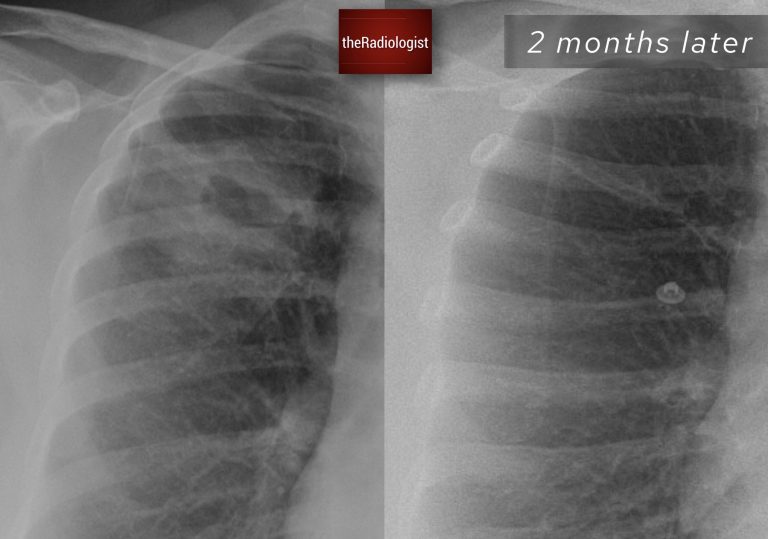

The patient was treated with antibiotics, and a follow-up X-ray showed complete resolution of the lesion, confirming an infective etiology.

Follow up chest X-Ray at 2 months shows resolution of the right sided cavitating lesion.